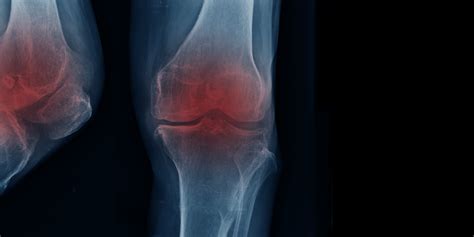

Alright guys, let’s start with the basics. Arthritis , in its simplest terms, means inflammation of the joints. But man, it’s a complex beast! There are over 100 different types of arthritis, with the most common ones being osteoarthritis (the wear-and-tear kind), rheumatoid arthritis (an autoimmune disease), psoriatic arthritis, and gout. Each type has its own unique way of messing with your joints, causing pain, stiffness, swelling, and sometimes, a whole lot of other nasty symptoms that can spread beyond the joints, like fatigue and fever. The chronic inflammation and damage that occur with these conditions can progressively erode cartilage, deform joints, and severely limit range of motion and function. Imagine trying to do everyday things like opening a jar, typing, walking, or even just getting out of bed when your joints are screaming in pain and won’t cooperate. It’s tough, right? This progressive nature and the debilitating pain are the main reasons why arthritis can significantly impair an individual’s ability to perform work-related activities and activities of daily living, ultimately leading to disability. We’re talking about a loss of functional capacity that can prevent someone from earning a living or maintaining their independence. It’s not just about feeling a bit sore; it’s about a substantial and often permanent reduction in your body’s ability to do what it needs to do.

Let’s zero in on osteoarthritis (OA) first, because it’s the most common type, affecting millions of people worldwide. Think of your joints like a well-oiled machine with shock absorbers. In OA, the protective cartilage that cushions the ends of your bones gradually wears down. Over time, this can lead to bone rubbing against bone, causing that characteristic pain, stiffness, and reduced flexibility. While OA often affects weight-bearing joints like knees, hips, and spine, it can also impact hands and other joints. For many, OA starts subtly, but as it progresses, the pain becomes more constant and severe. This can make simple tasks incredibly difficult. Imagine trying to stand for long periods, walk to the grocery store, or even just grip a pen to write. When the joints involved are critical for your job – say, you’re a construction worker, a nurse, or a retail associate who spends hours on their feet – OA can quickly make your job impossible. The physical demands of many occupations become insurmountable, leading individuals to consider disability. The long-term effects of OA can include chronic pain that doesn’t respond well to medication, joint deformities that further restrict movement, and significant loss of mobility. This isn’t something that just goes away; it’s a chronic condition that often requires ongoing management and can significantly impact your quality of life, pushing many towards seeking disability support because their capacity to work and function is severely compromised.